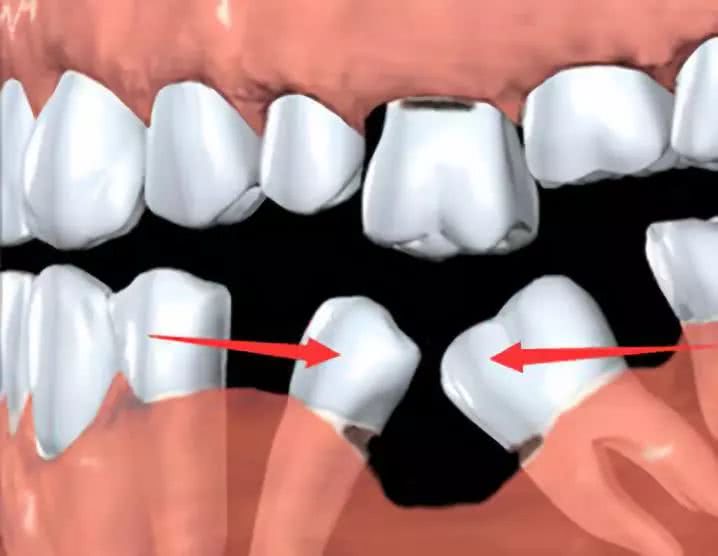

2、危害邻牙

牙齿承受的咀嚼力是有一定限度的,当个别牙齿缺失后,咀嚼力集中在余留牙上,由于咀嚼力超过了余留牙的承受限度,致使余留牙齿造成创伤而产生牙周膜水肿、牙龈萎缩、牙槽骨吸收、牙齿松动等牙周疾患。

牙齿松动导致牙空隙相应变大,咬合关系和牙齿排列出现错乱,致使剩余牙齿失去正常的邻接关系,造成食物嵌塞,进一步导致牙周病,形成恶性循环。